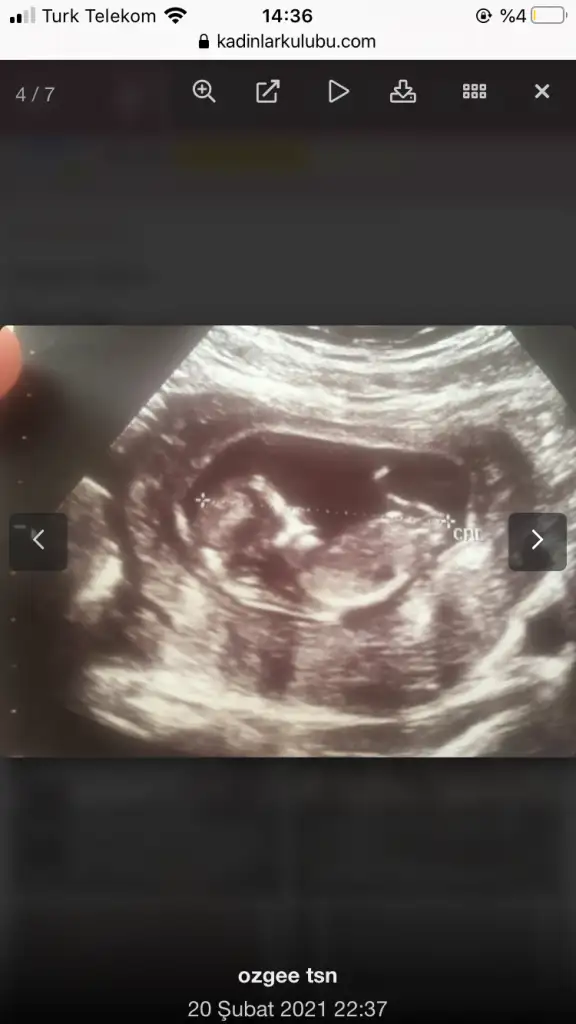

Ramzi teorisine göre ( bilimsel bir araştırma sonucuymuş ve %85 doğruluğu varmış). İlk 6-8 haftalık ultrason görüntüsüne göre bebeğin kesenin içersinde soldan ya da sağdan girişine göre cinsiyet tahmini yapılıyor. Bilimsel olunca tecrübeli annelerimiz yada anne adaylarımızdan yardım istiyoruz. Doğruluğu var mı öğrenmek adına :) Bizleri aydınlatırsanız çok seviniriz. bu teorieye göre;

Vajinal muayeneyle bakıldıysa eğer;

Sağdan girmiş gözüküyosa aslında solmuş ve ERKEK,

Soldan girmiş gözüküyosa aslında sağmış ve KIZ ,

Karından bakıldıysa eğer,

Soldan girmiş gözüküyosa gerçektede solmuş ve ERKEK,

Sağdan girmiş gözüküyosa gerçekte de sağmış ve KIZ,

Benimkinede bakarmisiniz 7 haftalikti burda karindan ultrasyonPlesanta solda bebekte solda karindan ultrasyonsa erkek